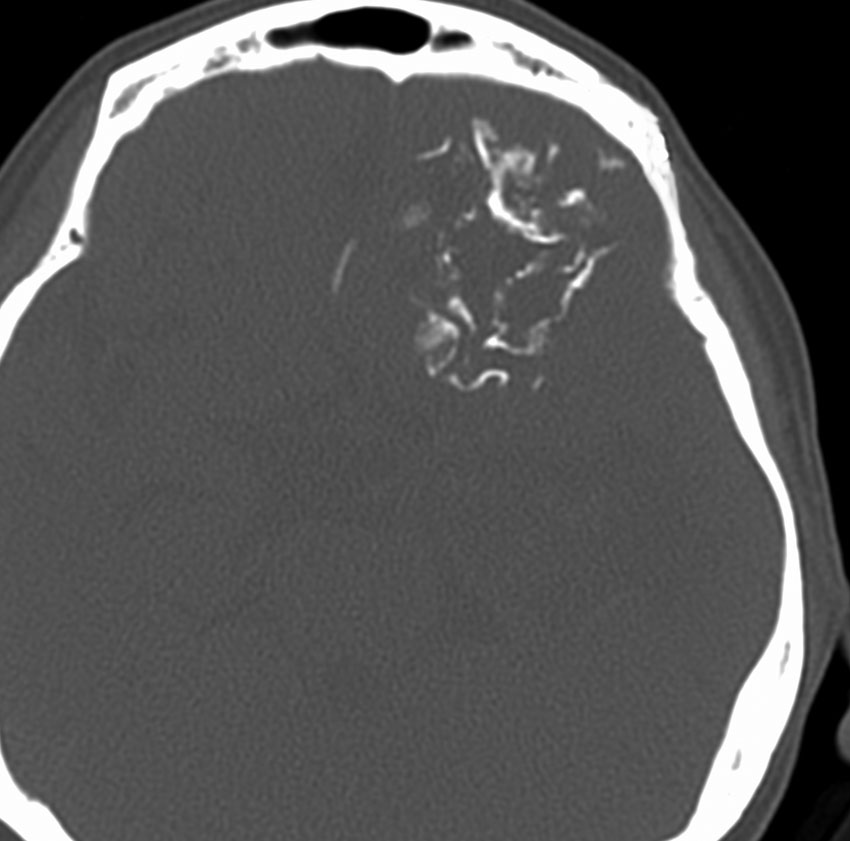

極めて高度な石灰化:脳石 brain stone

左は通常のCT,右は骨条件CTです。左前頭葉に巨大な石灰化を伴う乏突起膠腫があります。病理組織像は基本的にはグレード2です。石の塊のようにみえるので braine stoneと呼ばれ,CT eraでは oligodendrogliomaの hallmarkと言われました。